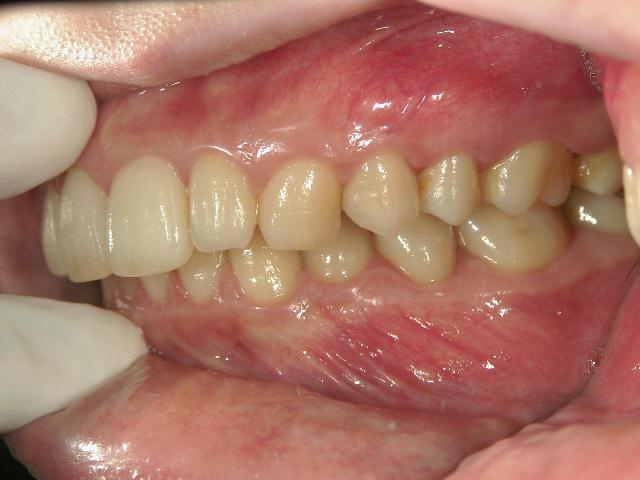

矯正歯科 治療前

矯正歯科 治療前 左